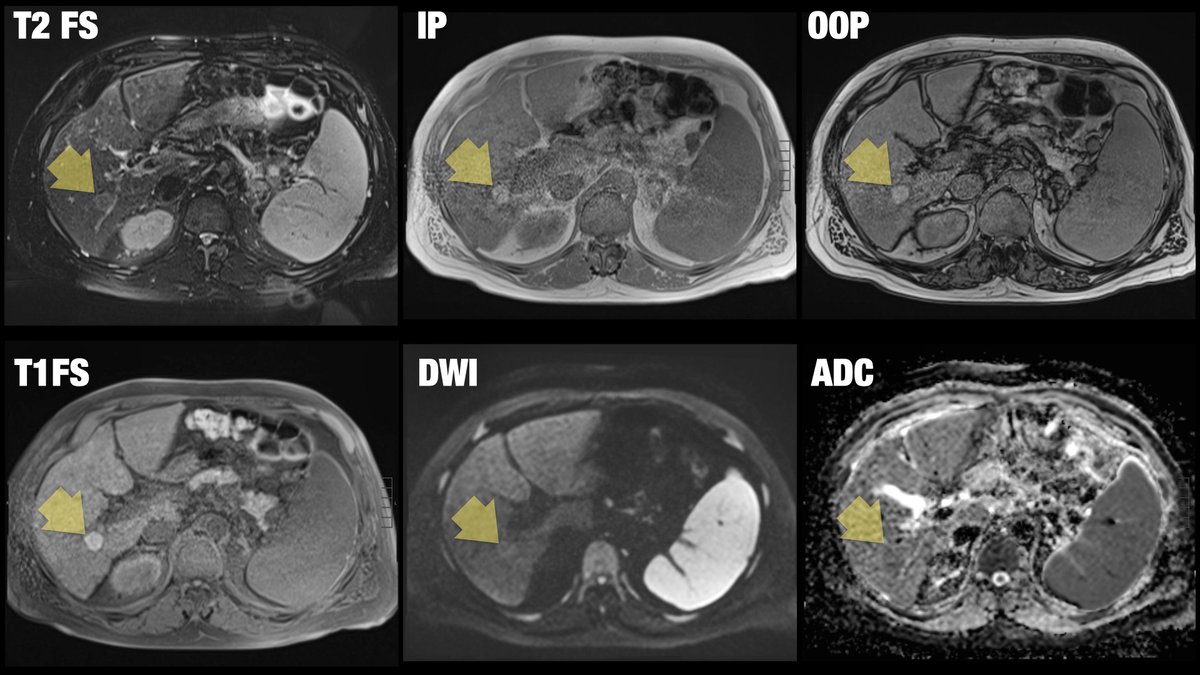

60-year-old male patient with history of cirrhosis undergoes HCC screening with non contrast MRI (patient refuses IV gadolinium due to hives)... Diagnosis? Next step? @BrighamRad @FOAMrad @SAR_RFS @futureradres @ARRS_Radiology @Abdominal_Rad @CBRadiologia #MedEd

Full disclosure: I lost the bet and did not get this one right... 🤨 can you? 59-year-old male patient with remote history of melanoma... diagnosis?